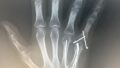

右手薬指及び小指の中手骨骨折する前の演奏動画